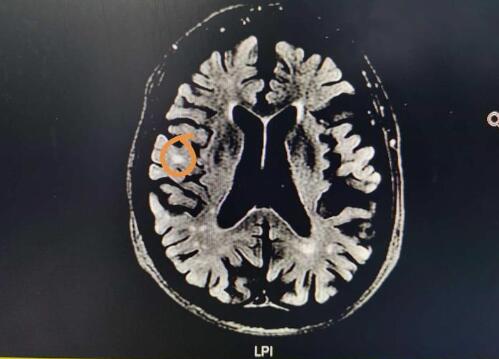

脑白质是大脑内部神经纤维聚集的地方,片子里白乎乎的显示叫脑白质高信号。

“脑白质高信号是大脑组织变性、衰老的一种指标,高信号多的大脑我们就预测可能会老化得快,少的则老化得较慢。”舒震宇说。

随后研究组运用计算机图像分析技术(影像组学),提前4年发现了脑白质高信号,就是从现在“貌似”正常的核磁共振图像中,预知哪些区域今后可能转化为脑白质高信号,并大致描绘出转化的范围和速度。这项预测的准确性达到了0.84-0.86(满分为1)。

脑白质高信号是一种医学专业描述,并非疾病名称。从医学角度讲,颅脑磁共振图像出现脑白质高信号,表明有慢性的脑血管损伤。磁共振图像中颜色越白就代表磁共振信号强度越高,因此只要看到某些区域有一个个的小白点或者是大片的白色斑块就说明脑白质发生了损伤。